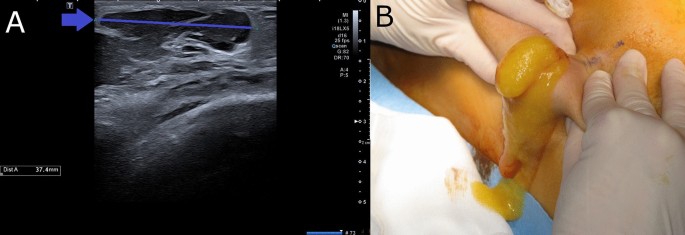

AQUAfilling este o substanță gelatinoasă folosită pentru augmentarea anumitor zone ale corpului, cum ar fi fesele sau buzele. Deși este promovată ca o alternativă mai puțin invazivă față de implanturi, AQUAfilling poate provoca reacții adverse severe, inclusiv inflamații, infecții și migrarea substanței în alte părți ale corpului.

În cazul Antoniei, reacțiile adverse au fost atât de grave încât au necesitat intervenții chirurgicale multiple pentru îndepărtarea completă a produsului. Acest lucru evidențiază faptul că orice procedură estetică trebuie făcută cu mare atenție, sub supravegherea unui medic specialist și după o evaluare riguroasă a riscurilor.